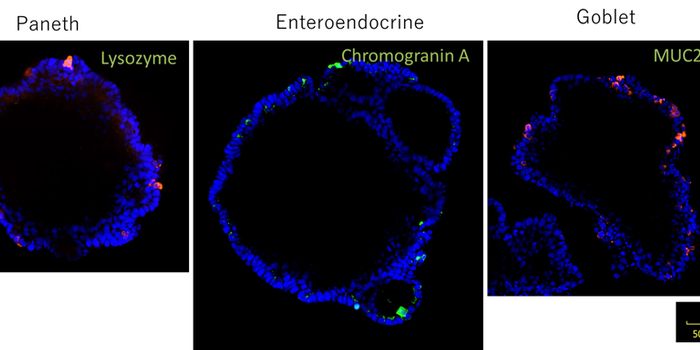

APR 24, 2023Cell & Molecular BiologyPublished by Bindi M. Doshi, PhD on Mar 17, 2023 Organoids are 3D structures made up of cells that replic ...